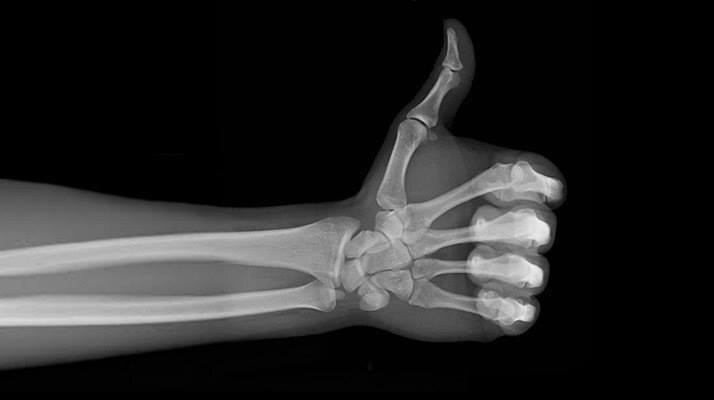

ПРОДУКТЫ ДЛЯ УКРЕПЛЕНИЯ КОСТЕЙ!

Для здоровья наших костей требуется целый набор питательных веществ: кальций, фосфор, магний, цинк, марганец, медь и витамин D. Причем действуют они именно в связке.    Конечно, важнейший элемент, без которого невозможны крепкие и здоровые кости, зубы и суставы — это кальций. Кроме того, систематическое поступление микроэлемента в организм снижает уровень холестерина, регулирует жировой обмен, улучшает работу сердца и служит профилактикой ишемической болезни.    При дефиците кальция быстро наступает утомляемость, раздражительность, начинают болеть кости. Затем развиваются такие болезни, как остеопороз, остеохондроз, артроз. Ногти делаются ломкими и хрупкими, волосы тускнеют, а зубы выкрашиваются.    Оказывается, остеопорозом страдают даже тридцатилетние: костная ткань становится непрочной, деформируется и не справляется с нагрузкой, происходят частые переломы. Остеопорозом чаще всего болеют женщины — мы ведь теряем кальций во время месячных, беременности и грудного вскармливания, а вос